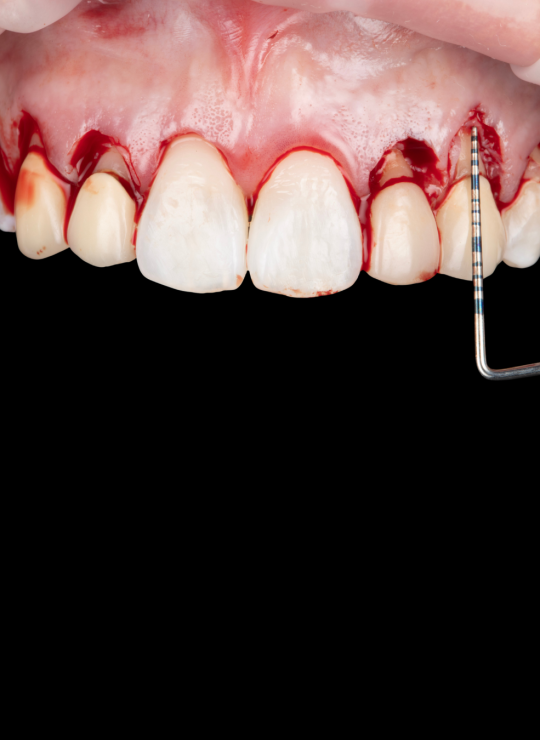

Surgical techniques for aesthetic crown lengthening: flap design, bone recontouring, and suturing

Flap reflection, bone removal, suturing on models or pig jaws

Diagnostic protocols: periodontal sounding, radiographic assessment, crown-to-root ratio considerations

Surgical techniques for posterior crown lengthening: flap design modifications, osseous recontouring, suturing

Posterior flap design, osseous recontouring, restorative margin management on models